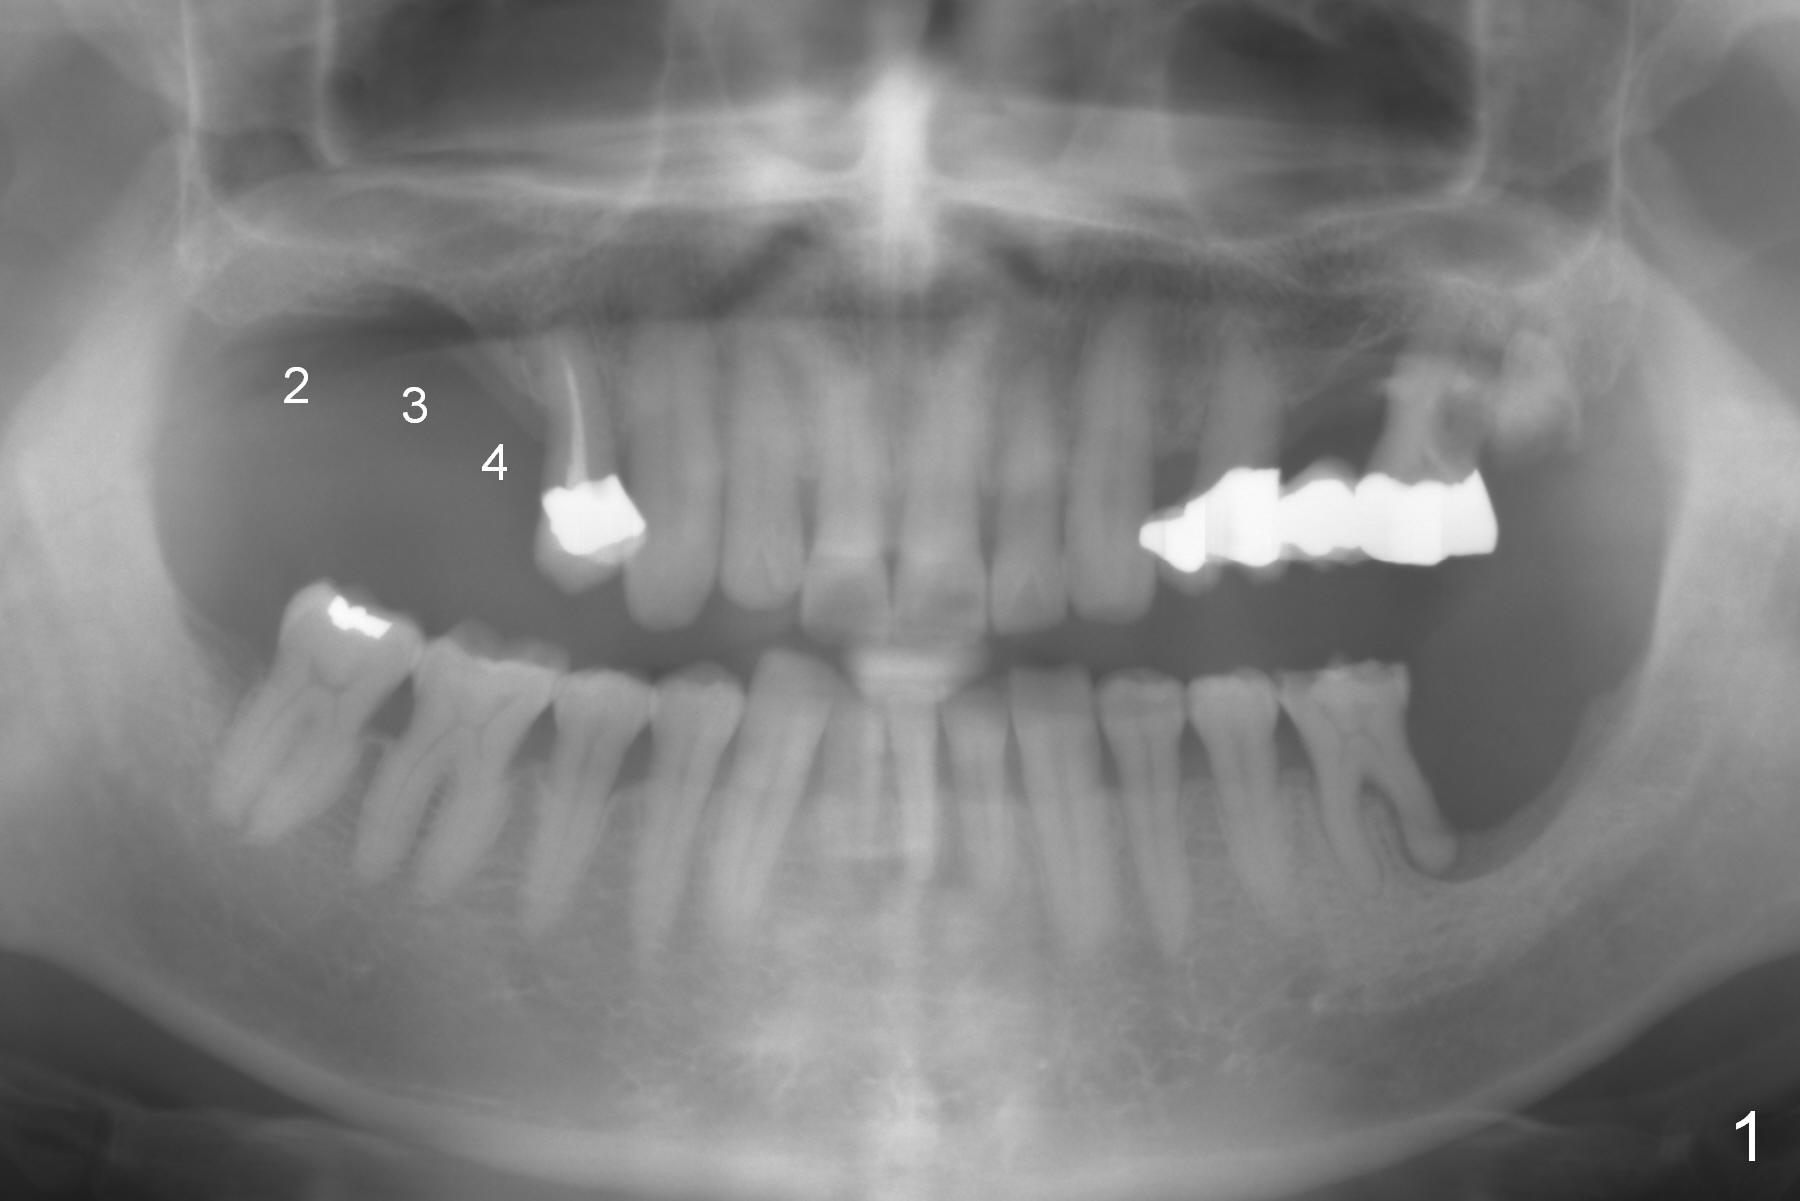

Fig.1: Preop panoramic X-ray.